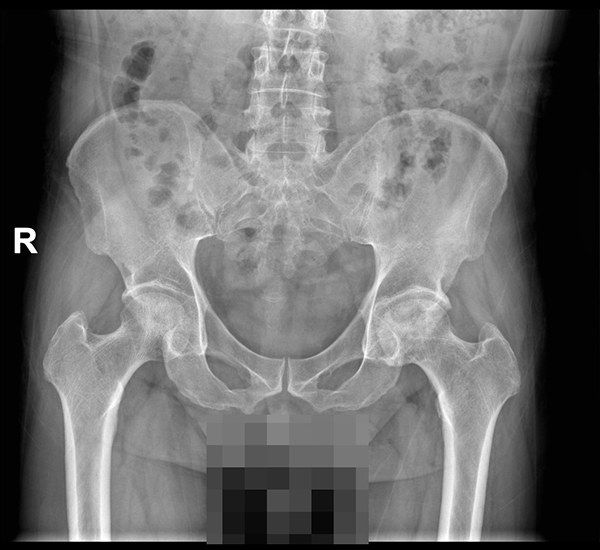

心脏移植后九年再遇股骨头坏死,多学科团队共筑关节重生之路

近日,南方医科大学南方医院关节与骨病科张洋主任医师团队成功为一名心脏移植术后9年的股骨头坏死患者实施全髋关节置换术。该手术突破了移植患者长期免疫抑制、心功能代偿等多重壁垒,团队通过围手术期多学科协同管理,实现精准假体植入与快速康复。患者术后5天独立行走,围术期血红蛋白水平保持稳定,心功能及肾功能均维持在术前基线状态,创造了该群体关节置换康复新纪录。长期服用药…